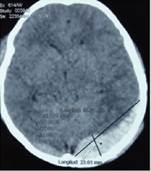

Según la escala de Marshall el paciente presenta una lesión difusa de tipo IV, se aprecia una desviación de la línea media superior a 5 mm (Ver figura 1). En la tomografía se puede observar en la ventana ósea: fractura parietooccipital y en la ventana parenquimatosa una lesión hiperdensa biconvexa que corresponde al hematoma epidural supra e infratentorial que abarca 20 cortes de la tomografía ubicado en la fosa posterior en la región occipital y parietal, las medidas de este hematoma son 10 cm de alto, 8,5 cm de largo y 2,3 cm de ancho (Ver figura 2). Para la estimación del volumen se aplica la Fórmula ABC/2. Donde A corresponde a= longitud máxima de la lesión (en cm) de la TC, B = ancho perpendicular de A en el mismo corte de la tomografía y C = número de cortes multiplicado por el grosor del corte, aplicándolos a nuestros valores tenemos un total de 97,5 ml; es importante entender que el mecanismo provee información crucial para el entendimiento de la lesión. El paciente sufrió una colisión contra el pavimento luego de salir proyectado de su bicicleta, dando una vuelta aproximada de 270° para finalmente impactar con la región occipital en contra de la porción rocosa de la carretera, lo cual nos permite concluir con total seguridad que esta fue la causa del hematoma epidural. Posterior a ello se elaboró un plan de tratamiento en el cual se decide su operación quirúrgica en el tercer día de hospitalización. Para contextualizar el caso: paciente ingresa con un diagnóstico de Traumatismo craneoencefálico moderado con Glasgow: 12/15, Edema Cerebral, Hematoma epidural supra e infratentorial.